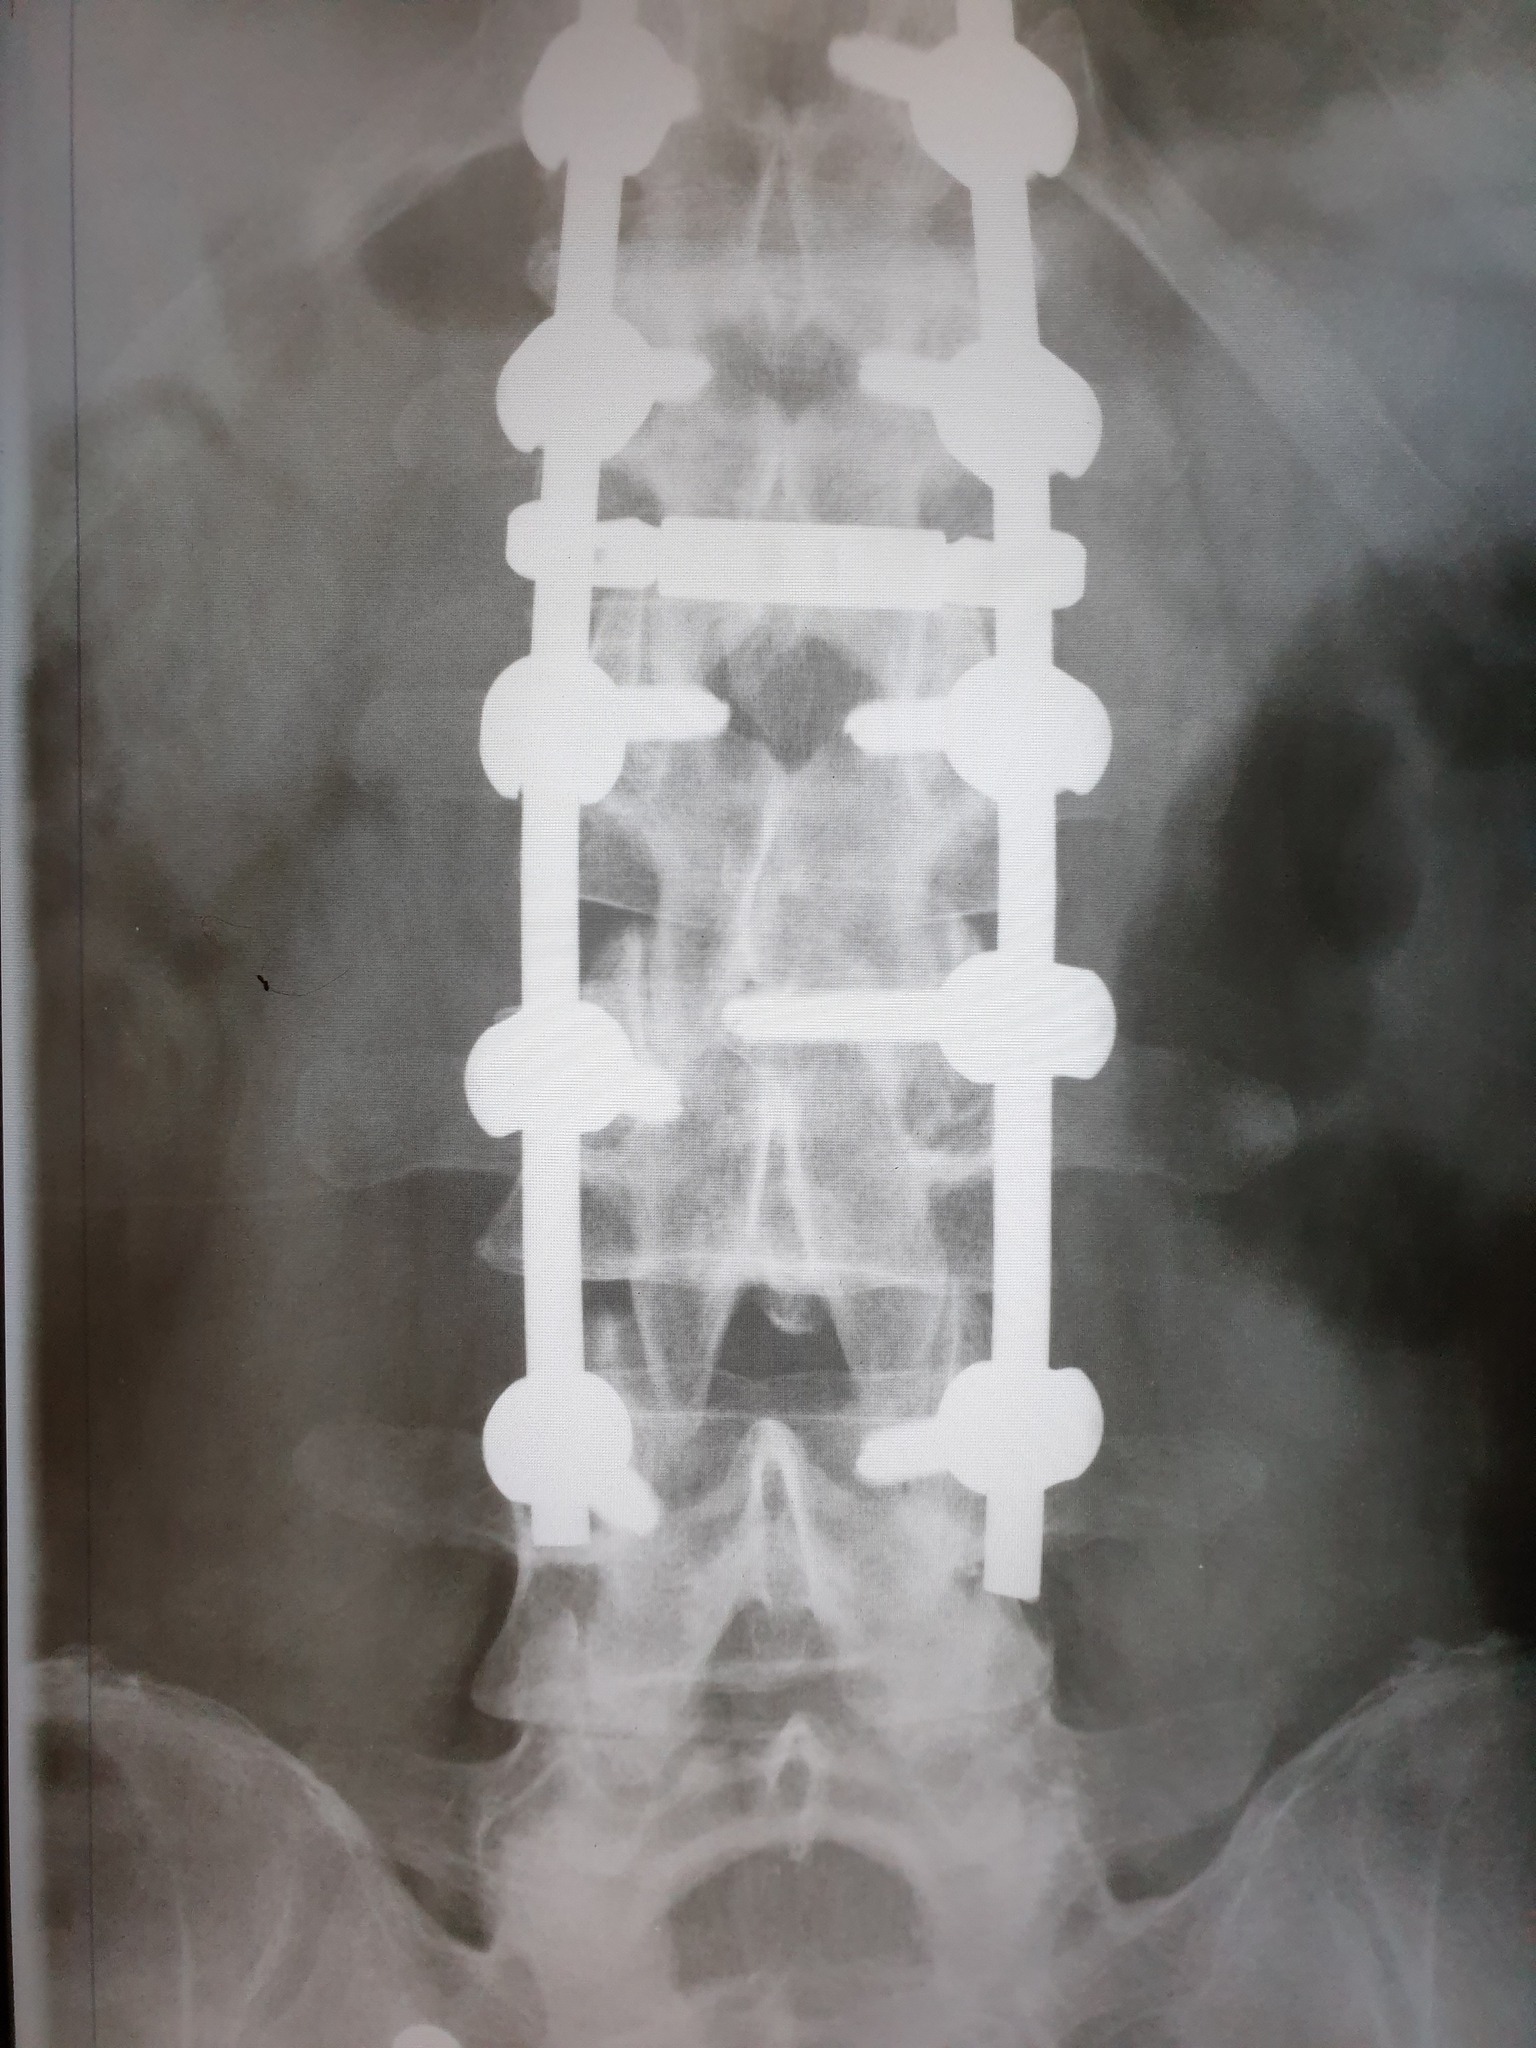

Nakon što je 11. februara doživio povredu na radnom mjestu, tačnije nakon što je pao sa lotri i slomio kičmu na dva mjesta Nino Katić je odlučio da progovori i sa svima podijeli svoje iskustvo, ali i pokaže zastrašujuće povrede koje je zadobio.

– Šta dobiješ u “Centrumu” kada zbog njihovog neispravnog sredstva za rad slomiš kičmu na dva mjesta i ostaneš invalid? Pa kod neljudi dobiješ otkaz, i to poštom – rekao je Katić, a zatim je opisao šta je dovelo do teške nesreće koja se dogodila 11. februara, ali i svemu što je slijedilo nakon tog dana.

– Došao je i 11. februar, taj crni 11. kada sam pao sa lotri, samo pukoše ispod mene i završio sam sa dvostrukim lomom kičme. Inspekciju nisu zvali, jedva je i Hitna pozvana, a kažu prva riječ šefova je bila: “Jeste li morali zvati Hitnu?”, Nakon toga me je zamjenica porodične doktorke oštetila svojim neradom jer mi nije htjela na vrijeme izdati uputnicu za ljekarsku komisiju na koju sam zbog toga zakasnio dva dana i uslijed čega mi je ljekarska komisija promjenila status iz “povreda na radu: DA” u “povreda na radu: NE”, znači svjesno se lagalo na zvaničnom dokumentu – objasnio je Katić za Srpskainfo.